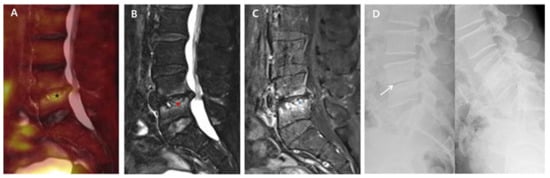

Back pain caused by the destruction of intervertebral discs and endplates may continue during the post-treatment course of PVO even after successful antibiotic therapy. Although some PVO lesions presenting back pain related with sustained instability may require additional fusion surgery, this study showed that most PVO lesions were stabilized with intervertebral autofusion or maintained joint function without any instability after successful antibiotic therapy. At 6-month follow-up, intervertebral autofusion was achieved in 59.3% of patients, and instability was identified in only 6.2% (2/32) of patients. However, there is still insufficient literature on the rate of autofusion or instability requiring surgical treatment. In this study, 14 patients were excluded because of insufficient radiological data at six-month follow-up, which can be a major limitation in obtaining higher levels of evidence; however, no patient was treated with additional fusion surgery. Hence, we can suggest that a large portion of intervertebral damage caused by PVO can be treated with intervertebral autofusion or preserved as an intervertebral joint after successful antibiotic therapy. Compared to group B with no intervertebral autofusion at six-month follow-up, group A with intervertebral autofusion showed more extensive edematous changes to vertebral bodies and a higher 18F-FDG uptake on the intervertebral structure immediately after antibiotic therapy (Figure 1 and Figure 2).

Figure 2. 18F-FDG-PET/MRI immediately after successful antibiotic therapy and radiographs at six-month follow-up in a patient with no autofusion (group B). A 73-year-old male patient shows PVO of L4–5 on 18F-FDG-PET/MRI with SUVmax 3.83 of the intervertebral structure (black asterisk) after 56 days of ceftriaxone (ESR 37 mm/h and CRP 0.16 mg/dL). In the distribution pattern of the PVO lesion, 18F-FDG uptake (black asterisk) on 18F-FDG-PET (A), high signal intensity (red asterisk) on T2FS MRI (B), and contrast enhancement (black asterisk) on T1C MRI (C) are limited around the destroyed disc and endplates rather than the bone and soft tissue with almost improved discitis (grade II). The dynamic radiographs at six-month follow-up (D) show an unstable intervertebral structure presenting with an intervertebral gap (white arrow), and there is no definite formation of syndesmophyte. 18. F-FDG-PET/MRI, 18F-fluorodeoxyglucose positron emission tomography/magnetic resonance imaging; SUVmax, maximum standardized 18F-FDG uptake value; PVO, pyogenic vertebral osteomyelitis; CRP, C-reactive protein (normal range of <0.5 mg/dL); ESR, erythrocyte sedimentation rate (normal range of <25 mm/h); T2FS, T2-weighted fat saturation; T1C, T1-weighted contrast; MRI, magnetic resonance imaging.